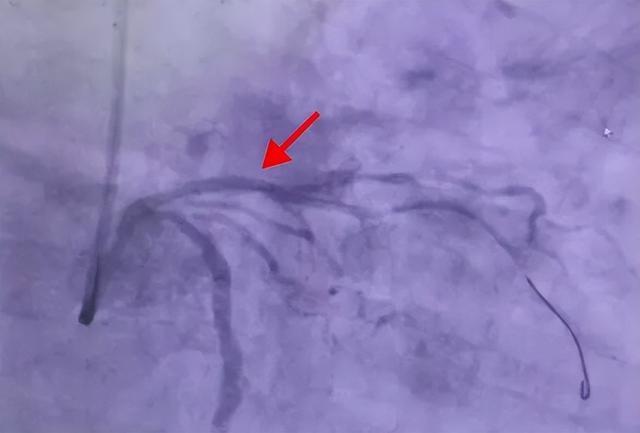

随后,介入团队凭借精湛技术,顺利完成球囊扩张及药物支架植入手术,彻底疏通堵塞血管,恢复心脏正常血流。术后复查显示,支架贴合完好,血管残余狭窄为0%,手术圆满成功。

(▲PCI术后前降支近端血管开通,无残余狭窄,血流TIMI3级)